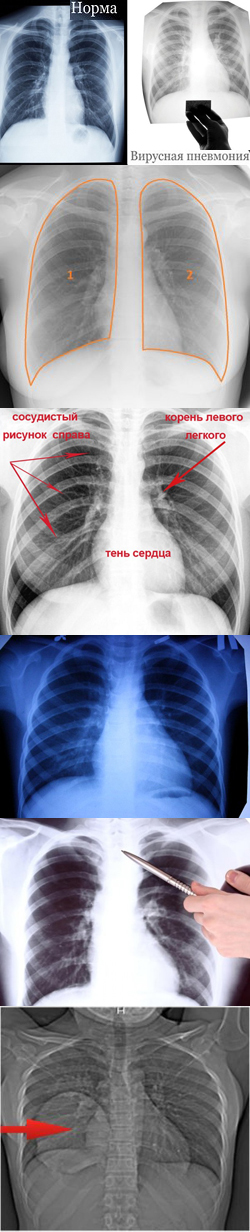

Рентгенологические изображения и синдромы патологии легких

Раздел: Кадры-подсказки